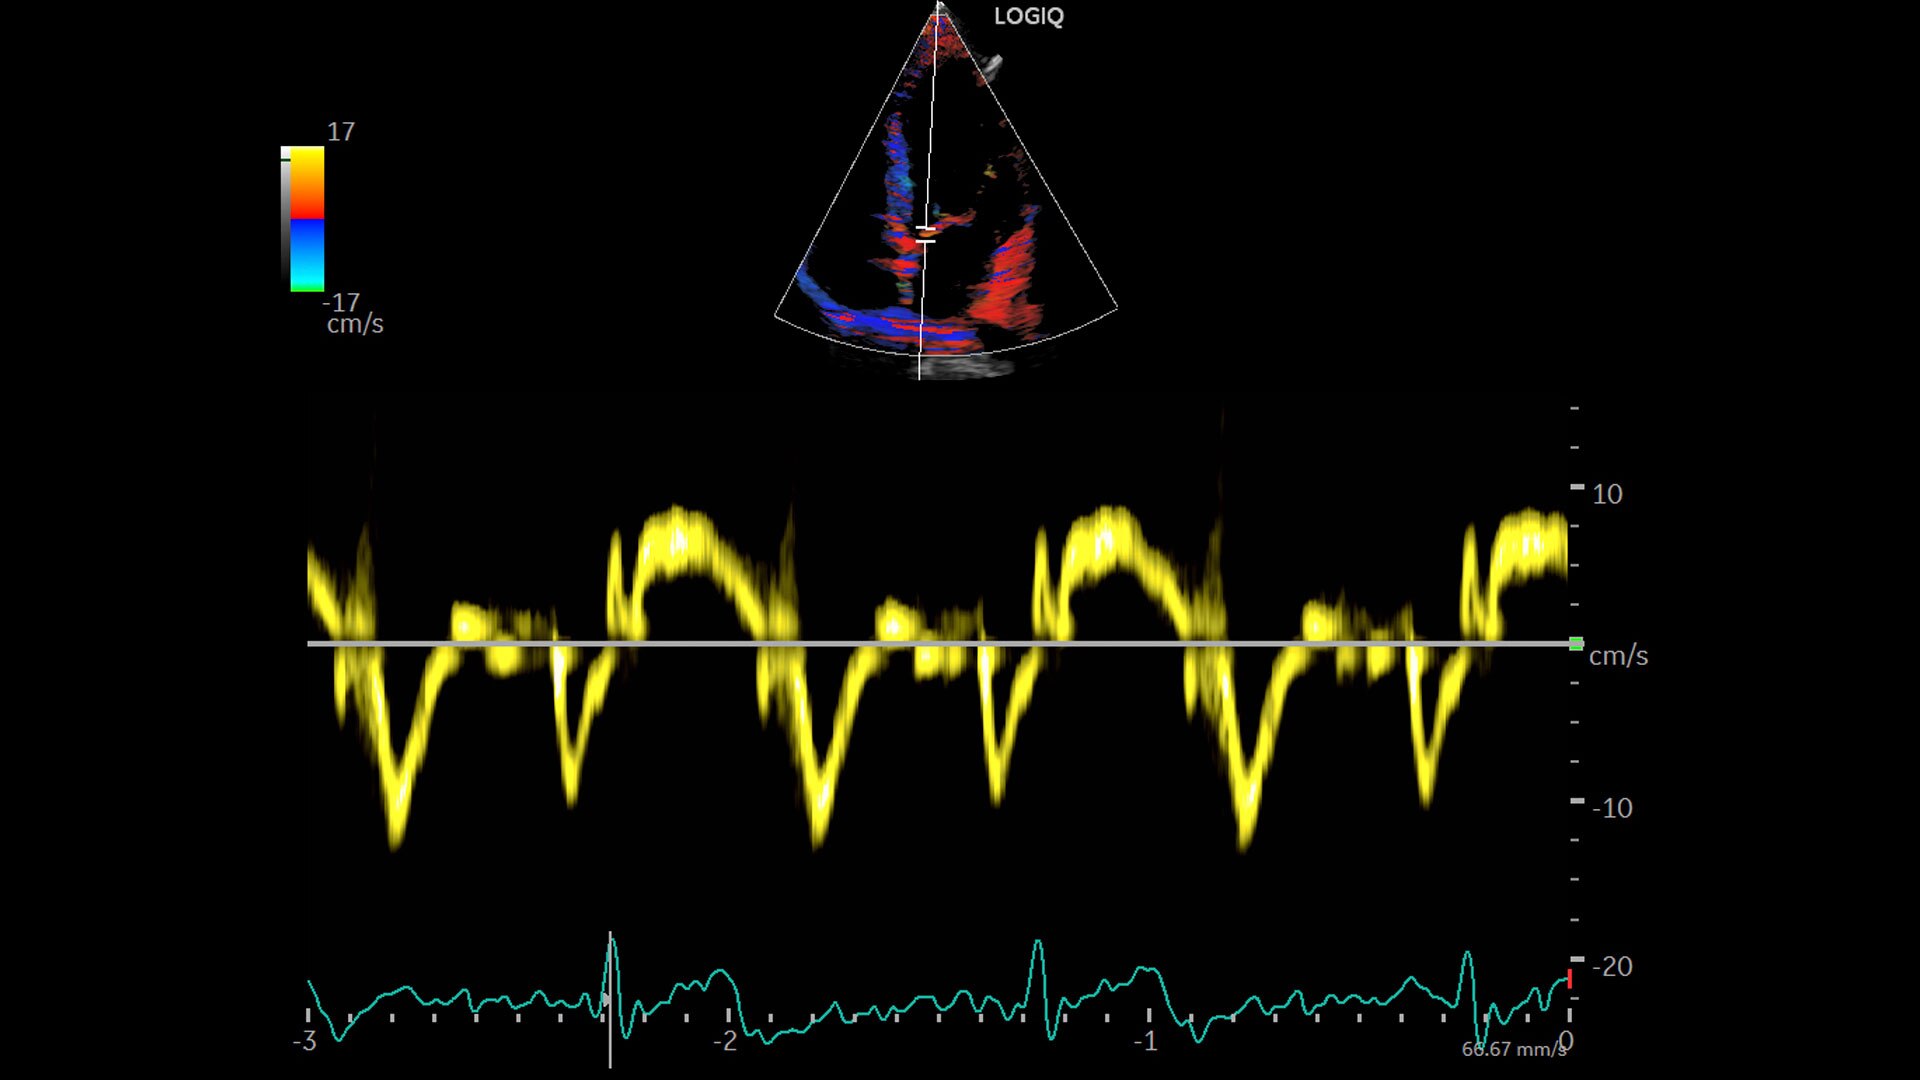

Multi-purpose capabilities, including liver, cardiac, OB/GYN, vascular, breast, thyroid, musculoskeletal, urologic, and pediatric studies.

Advanced imaging and visualization tools, including:

• 2D Shear Wave Elastography

• Ultrasound-Guided Attenuation Parameter (UGAP)

• CEUS

• B-Flow and B-Flow Color

• 3D/4D with SonoRenderlive

• Stress Echo